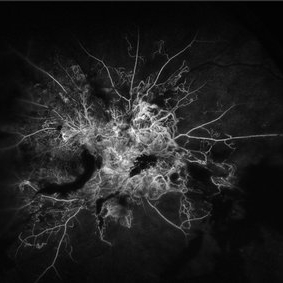

Proliferative Diabetic Retinopathy

Oct 13 2024 by Brandon I Fram, MD, BS

28 year-old with florid neovascularization of the disc and extensive nonperfusion imaged with fluorescein angiography

Condition/keywords: florid type PDR, fluorescein angiogram (FA), neovascularization of the disc (NVD), PDR, proliferative diabetic retinopathy (PDR)